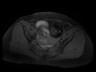

MR images demonstrate left ovarian mass containing fat and soft tissue. Left ovarian mass that contains: Fat (bright in T1 image and fat suppression in T1 fat sat and STIR images), soft tissue-dermoid plug (increased enhancement in T1+C fat sat images).

Conventional radiograph can show calcific and tooth components in the pelvis. An ovarian dermoid is seen as a unilocular cystic adnexal mass with some mural components on ultrasound. CT images demonstrate fat areas with very low Hounsfield values, fat-fluid level, calcification, Rokitansky protuberance. Pelvic MRI shows the presence of fat. Fat suppression technique is used to differentiate between ovarian dermoid cyst and hemorrhagic cyst. Dermoid cyst contains fat and its signal will be suppressed in T1 fat sat and STIR images (2, 3).